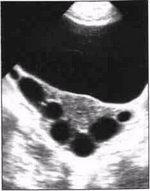

Рисунок 2. Много-камерный вариант гидросальпингса.

. Многокамерный вариант. Локализация такая же, как и при первом варианте, но с большим распространением в латеральном и медиальном направлениях за счёт более крупных размеров патологического очага и часто встречающегося двухстороннего поражения. На эхограммах (условия сканирования прежние, с элементами продольной эхолокации) в одной из параметральных областей с распространением в позадиматочное пространство лоцируется многокамерное жидкостное образование неправильной вытянутой формы, которая зависит от числа камер и степени распространенности процесса. Многокамерность образования обусловлена множественными перетяжками, возникающими либо вследствие перегибов маточной трубы, заполненной воспалительным экссудатом, либо за счет спаек, частично или полностью перекрывающих просвет трубы. Число камер (полостей) колеблется от 2 до 7. Стенки тонкие, контуры чёткие и неровные из-за выпячивания перерастянутых жидкостью стенок маточной трубы. Размеры варьируют в широких пределах, но во всех случаях длина гидросальпингса значительно больше его поперечника. В некоторых наблюдениях длина жидкостного образования достигает 150 мм. Структура содержимого однородная. Крайне редко в одной из полостей видны мелкие эхопозитивные включения линейной формы, низкой эхоплотности (фибрин, детрит), хорошо видимые при ТВ-сканировании. В отличие от других патологических многополостных жидкостных образований встречающихся в малом тазу, для многокамерного гидросальпингса характерно своеобразное расположение составляющих его камер - друг за другом, как звенья цепи. Этот симптом не может считаться патогномоничным, но безусловно является постоянным эхо-признаком данного вида экссудативного сальпингита. Матка не изменена. Яичник на стороне поражения не лоцируется, так как параметральная область и позадиматочное пространство, как правило, полностью заняты патологическим жидкостным объектом. Другой яичник без особенностей.Содержимое одной или нескольких полостей может быть неоднородным из-за множественных эхопозитивных включений, обычно скапливающихся у нижней стенки образования. Эти включения имеют линейный, точечный или нитевидный характер; морфологически - детрит и фибрин. Стенки такой полости (полостей) в 80% диффузно утолщены (до 6 мм) вследствие воспалительной инфильтрации и отёка. Указанная картина бывает при гнойном сальпингите, который, в случае многокамерного варианта гидросальпингса, является осложнением обычного экссудативного воспалительного процесса.